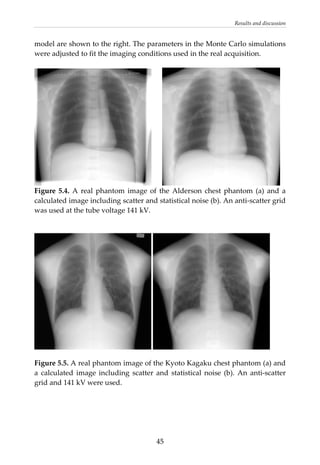

are present in real phantoms (see further figure 5.4).

26

Assessment of image quality

The  SKE/BV  task  was  addressed  in  papers  III  and  VI  were  the  task  was

detection of nodules at various positions in the lungs. In paper III, the size and

shape of the nodules corresponded to those used in the trial by Håkansson et